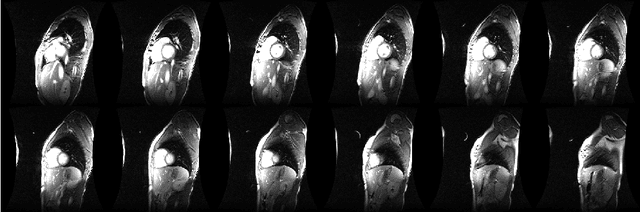

Abstract:In this paper, we introduce a dictionary learning based approach applied to the problem of real-time reconstruction of MR image sequences that are highly undersampled in k-space. Unlike traditional dictionary learning, our method integrates both global and patch-wise (local) sparsity information and incorporates some priori information into the reconstruction process. Moreover, we use a Dependent Hierarchical Beta-process as the prior for the group-based dictionary learning, which adaptively infers the dictionary size and the sparsity of each patch; and also ensures that similar patches are manifested in terms of similar dictionary atoms. An efficient numerical algorithm based on the alternating direction method of multipliers (ADMM) is also presented. Through extensive experimental results we show that our proposed method achieves superior reconstruction quality, compared to the other state-of-the- art DL-based methods.

Abstract:It has been recently shown that incorporating priori knowledge significantly improves the performance of basic compressive sensing based approaches. We have managed to successfully exploit this idea for recovering a matrix as a summation of a Low-rank and a Sparse component from compressive measurements. When applied to the problem of construction of 4D Cardiac MR image sequences in real-time from highly under-sampled $k-$space data, our proposed method achieves superior reconstruction quality compared to the other state-of-the-art methods.